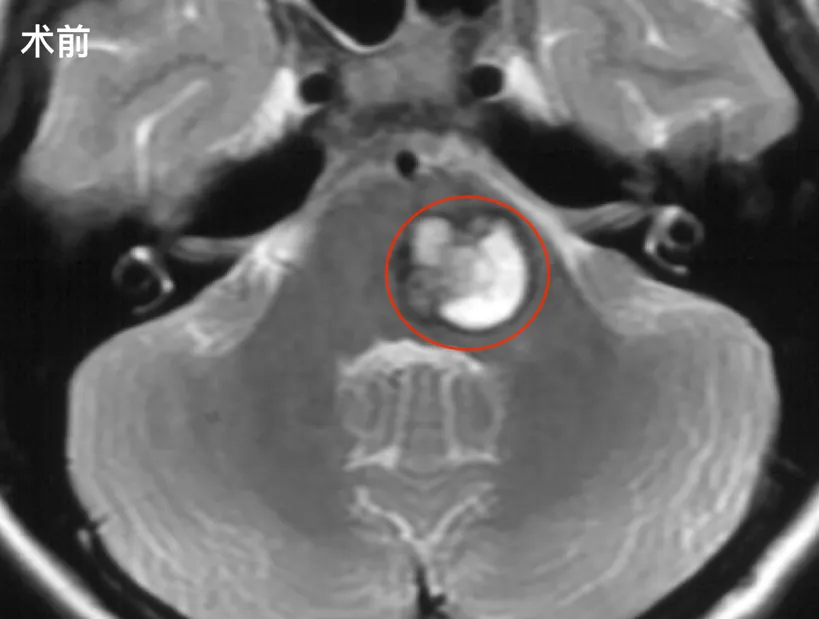

不是有希望才坚持,是坚持才有希望这是贝贝爸爸在女儿闯过鬼门关后,最常挂在嘴边的话。 一场突如其来的脑干海绵状血管瘤急性出血,让12岁的贝贝从疑似流感迅速坠入半身瘫痪、意识不清...